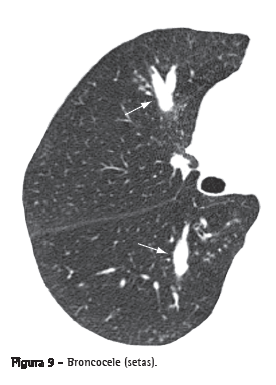

BroncoceleDilatação brônquica com retenção de secreções (impacção mucoide), geralmente causada por obstrução proximal, que pode ser congênita (por ex.: atresia brônquica) ou adquirida (por ex.: aspergilose broncopulmonar alérgica).(21) A broncocele apresenta-se como uma imagem tubular ou ramificada que se assemelha a um dedo de luva (Figura 9). Na TC, pode-se observar, em casos de atresia brônquica, uma redução da atenuação do parênquima distal à lesão.